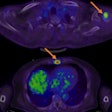

New PET tracer advances prostate cancer detection